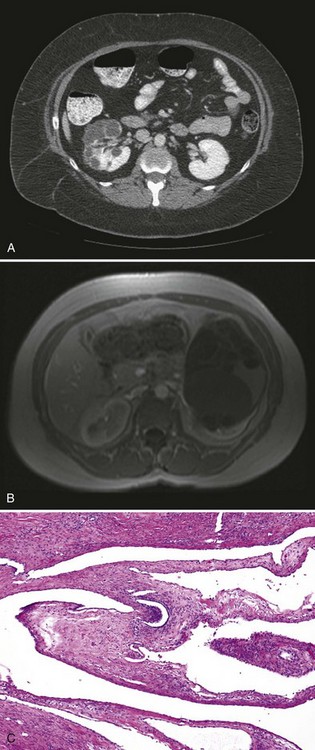

Radiologically, most cystic nephromas are solitary, centrally located, and widely variable in size (mean 9 cm) and commonly demonstrate curvilinear calcifications, herniation into the renal collecting system, and septal enhancement (Fig. 51–9A, B) (Madewell et al, 1983; Turbiner et al, 2007). Consequently, reliable radiologic differentiation between cystic nephroma and cystic RCC in adults or Wilms tumor in children is not possible (Vujanic et al, 2000).

Figure 51–9 Cystic nephroma. CT (A) and MR (B) images do not allow reliable distinction from cystic renal cell carcinoma or cystic Wilms tumor. C, The variably sized cystic spaces are lined by flattened epithelium (low magnification).

Histologically, cystic nephromas are well encapsulated by a thick fibrous pseudocapsule and are composed of cysts lined by flattened, cuboidal, or hobnail epithelium (see Fig. 51–9C). The stromal component can range from dense paucicellular collagen to markedly cellular fascicles of spindle cells, closely resembling ovarian stroma (Tamboli et al, 2000). Immunohistochemical studies reveal affinity of the epithelial component for cytokeratins, whereas stromal components frequently stain positive for CD10, calretinin, inhibin, estrogen, and progesterone receptors (Turbiner et al, 2007; Montironi et al, 2008).

Radiologic appearance of MEST is of a complex cystic renal mass, typically classifying these tumors as Bosniak class III to IV lesions, indistinguishable from cystic RCC (Fig. 51–10A) (Adsay et al, 2000). A typical MEST has a benign clinical course, but recently a case of malignant transformation to a sarcomatoid carcinoma and several cases of local recurrence of a malignant stromal component with a dismal clinical course have been described (Adsay et al, 2000; Nakagawa et al, 2004).

Figure 51–10 Mixed epithelial and stromal tumor. A, CT scan characteristics are not distinguishable from renal cell carcinoma. B, Gross photograph of a partial nephrectomy specimen demonstrating a well-circumscribed mass composed of variably sized cysts separated by thick white septa. C, Medium-power magnification shows cysts lined by hobnailed cells and spindle cell stroma.

Grossly, MEST appears encapsulated and ranges from 2 to 24 cm (mean 6 cm) (Adsay et al, 2000; Mai et al, 2007). Involvement of renal hilum and compression of the pelvicalyceal system is common, but gross infiltration of adjacent renal parenchyma is not seen (see Fig. 51–10B). The mesenchymal component is characterized by spindle cells showing variable degrees of smooth muscle, fibroblastic, or myofibroblastic differentiation with interspersed collagen bundles. The epithelial components vary from regular tubules to complex tubulopapillary structures with or without cystic dilatation, lined by cuboidal to flattened epithelium that may show clear cell changes and have a characteristic hobnail appearance (see Fig. 51–10C) (Adsay et al, 2000; Antic et al, 2006; Turbiner et al, 2007; Montironi et al, 2008). As in cystic nephroma, the epithelial components stain positive for cytokeratins whereas estrogen and progesterone receptor staining has been observed in the majority of the mesenchymal elements of MEST (Adsay et al, 2000).